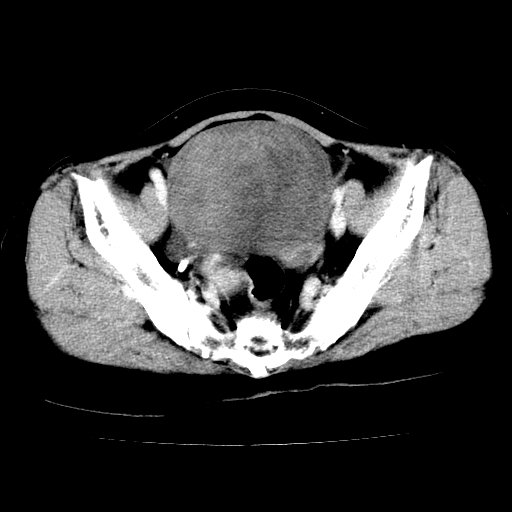

标题: CT24785:女,62岁,发现下腹部肿物半年。 [打印本页]

女,62岁,发现下腹部肿物半年,下腹部不适。

考虑肠系膜间质肉瘤或脐尿管癌可能性大。

卵巢囊腺瘤或囊腺癌,建议免疫组化实验

卵巢囊腺瘤或囊腺癌可能。

考虑附件囊腺癌。

考虑卵巢囊腺瘤或囊腺癌可能。